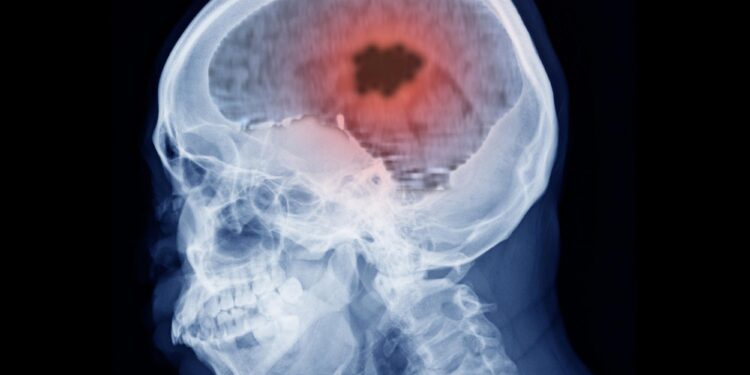

Prolonged use of sure progestogen hormone drugs has been linked to a better threat of intracranial meningioma, a kind of mind tumor, in keeping with analysis from France revealed not too long ago in The BMJ.

Meningiomas are principally non-cancerous tumors within the layers of tissue (meninges) that cowl the mind and spinal twine. Components corresponding to older age, feminine intercourse, and publicity to a few high-dose progestogens (nomegestrol, chlormadinone, and cyproterone acetate) are already identified to extend the chance of meningioma.